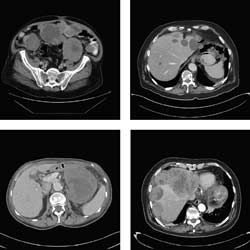

When computed tomography (CT) is used to follow imatinib-treated GISTs, responding tumors will demonstrate decreased density as measured by CT attenuation coefficient (Hounsfield unit [HU]). Paradoxically, such tumors might also show an increase in size, which is thought to reflect central necrosis and swelling of the tumor. Following GIST tumors by size alone is, therefore, inadequate. Choi and colleagues, from the MD Anderson Cancer Center, proposed a new CT criteria for assessing tumor response of GIST that includes not only size, but also incorporates tumor density changes by HU. To this end, a partial response (PR) would be defined as a decrease in size of >10% or a decrease in tumor density of HU >15% with no new lesions and progression would be defined as an increase in tumor size of >10% with failure to meet PR criteria by tumor density (HU) on CT. The remaining findings would be classified as new lesions, new intratumoral nodules, or increase in the size of the existing intratumoral nodules.35 Confirmation and validation of the Choi criteria is now underway by other research groups. The use of Choi criteria for non-GIST tumors has not been validated and RECIST is still used for non-GIST disease.